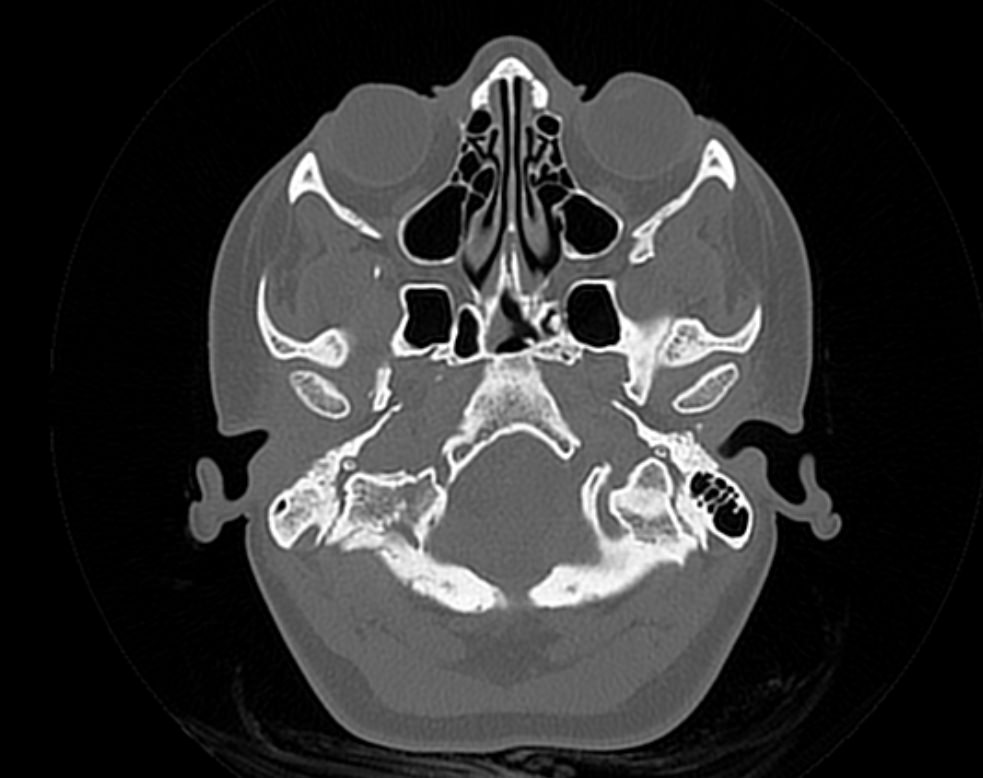

Черепная коробка состоит из мозгового и лицевого отделов. Лицевой череп образован костями верхней и нижней челюсти, скуловыми костями, решетчатой и клиновидной костью. Свод черепа состоит из височной, лобной, теменной и затылочной костей, соединенных между собой посредством межкостных швов.

Мультиспиральная компьютерная томография является наилучшим методом диагностики патологии костей черепа. В основе методики лежит использование рентгеновского излучения с последующей цифровой обработкой полученных данных и получения трехмерных реконструкций изображений.

Костная ткань отличается высокой плотностью и способна в большой степени поглощать рентгеновские лучи. Поэтому на послойных снимках, полученных при проведении мультиспиральной КТ черепа можно детально рассмотреть свод черепа, кости лица, основание черепа. Это позволяет с наибольшей точностью визуализировать различные объемные образования, такие как остеомы, дифференцировать фиброзную дисплазию или костные метастазы. Преимуществами методики КТ является отличная визуализация костных структур, быстрота выполнения процедуры и доступная цена. Все это делает КТ незаменимой при диагностике травматических повреждений (например переломов основания черепа или орбит), аномалий развития, при планировании оперативных вмешательств.